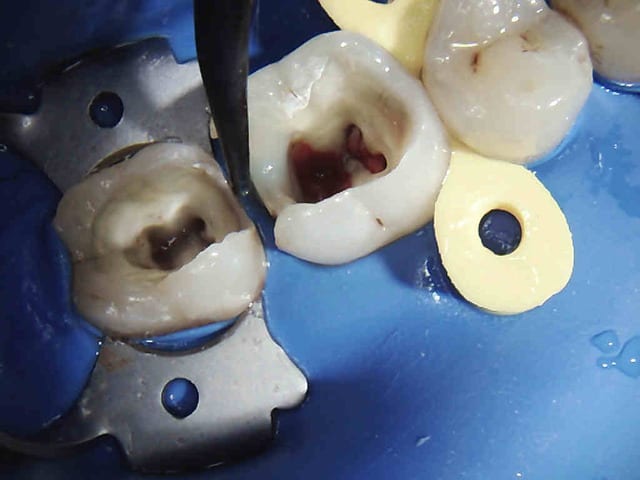

exemple :

Mobilité 31 (motif de la consultation); plan d'occlusion HS ( égression ).

Patient n'ayant pas 10 balles (mais qui travaille pourtant mais au smic malgré la moitié de cotisations sociales il a peanuts de remboursements) avec une mutuelle de merde en plus.

Amusez vous bien.

Endos + raser le secteur postérieur haut, rétablissement d'un plan d'occlusion correct avec de la fixe + Stellite bas.

Ca durera bien quelques années.